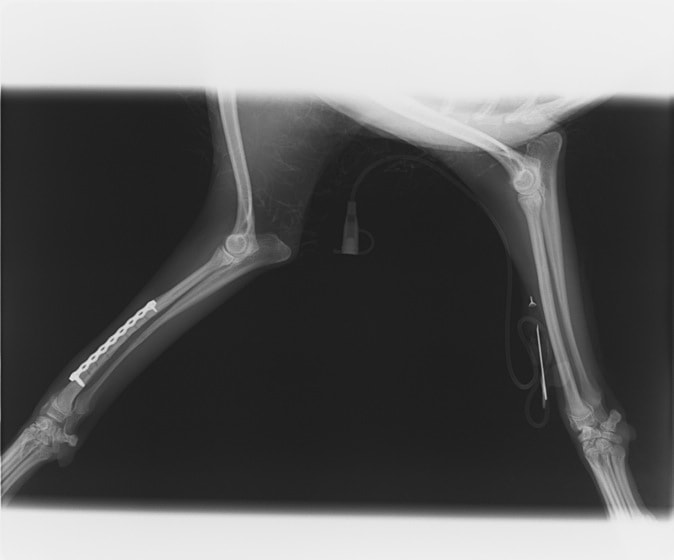

ペルシャ猫 11ヶ月齢 雄

他院にて左大腿骨遠位の成長板骨折(salter-harrisⅠ型)が認められており、治療相談を目的として来院。当院にて、キルシュナーワイヤーを用いたピンニングにより骨折部位の整復を行いました。術後の経過は良好で、現在も経過観察中です。

術前レントゲン

術後レントゲン

Arthrex社のターゲティングデバイスを用いてピンニングの位置を調整することで、確実な固定を行っています。当院ではこの手術器具以外にも、人の手術にも使用される様々な器具を導入し、手術精度を高め、また医療メーカーと新しい器具の開発、試作にも取り組んでおります。